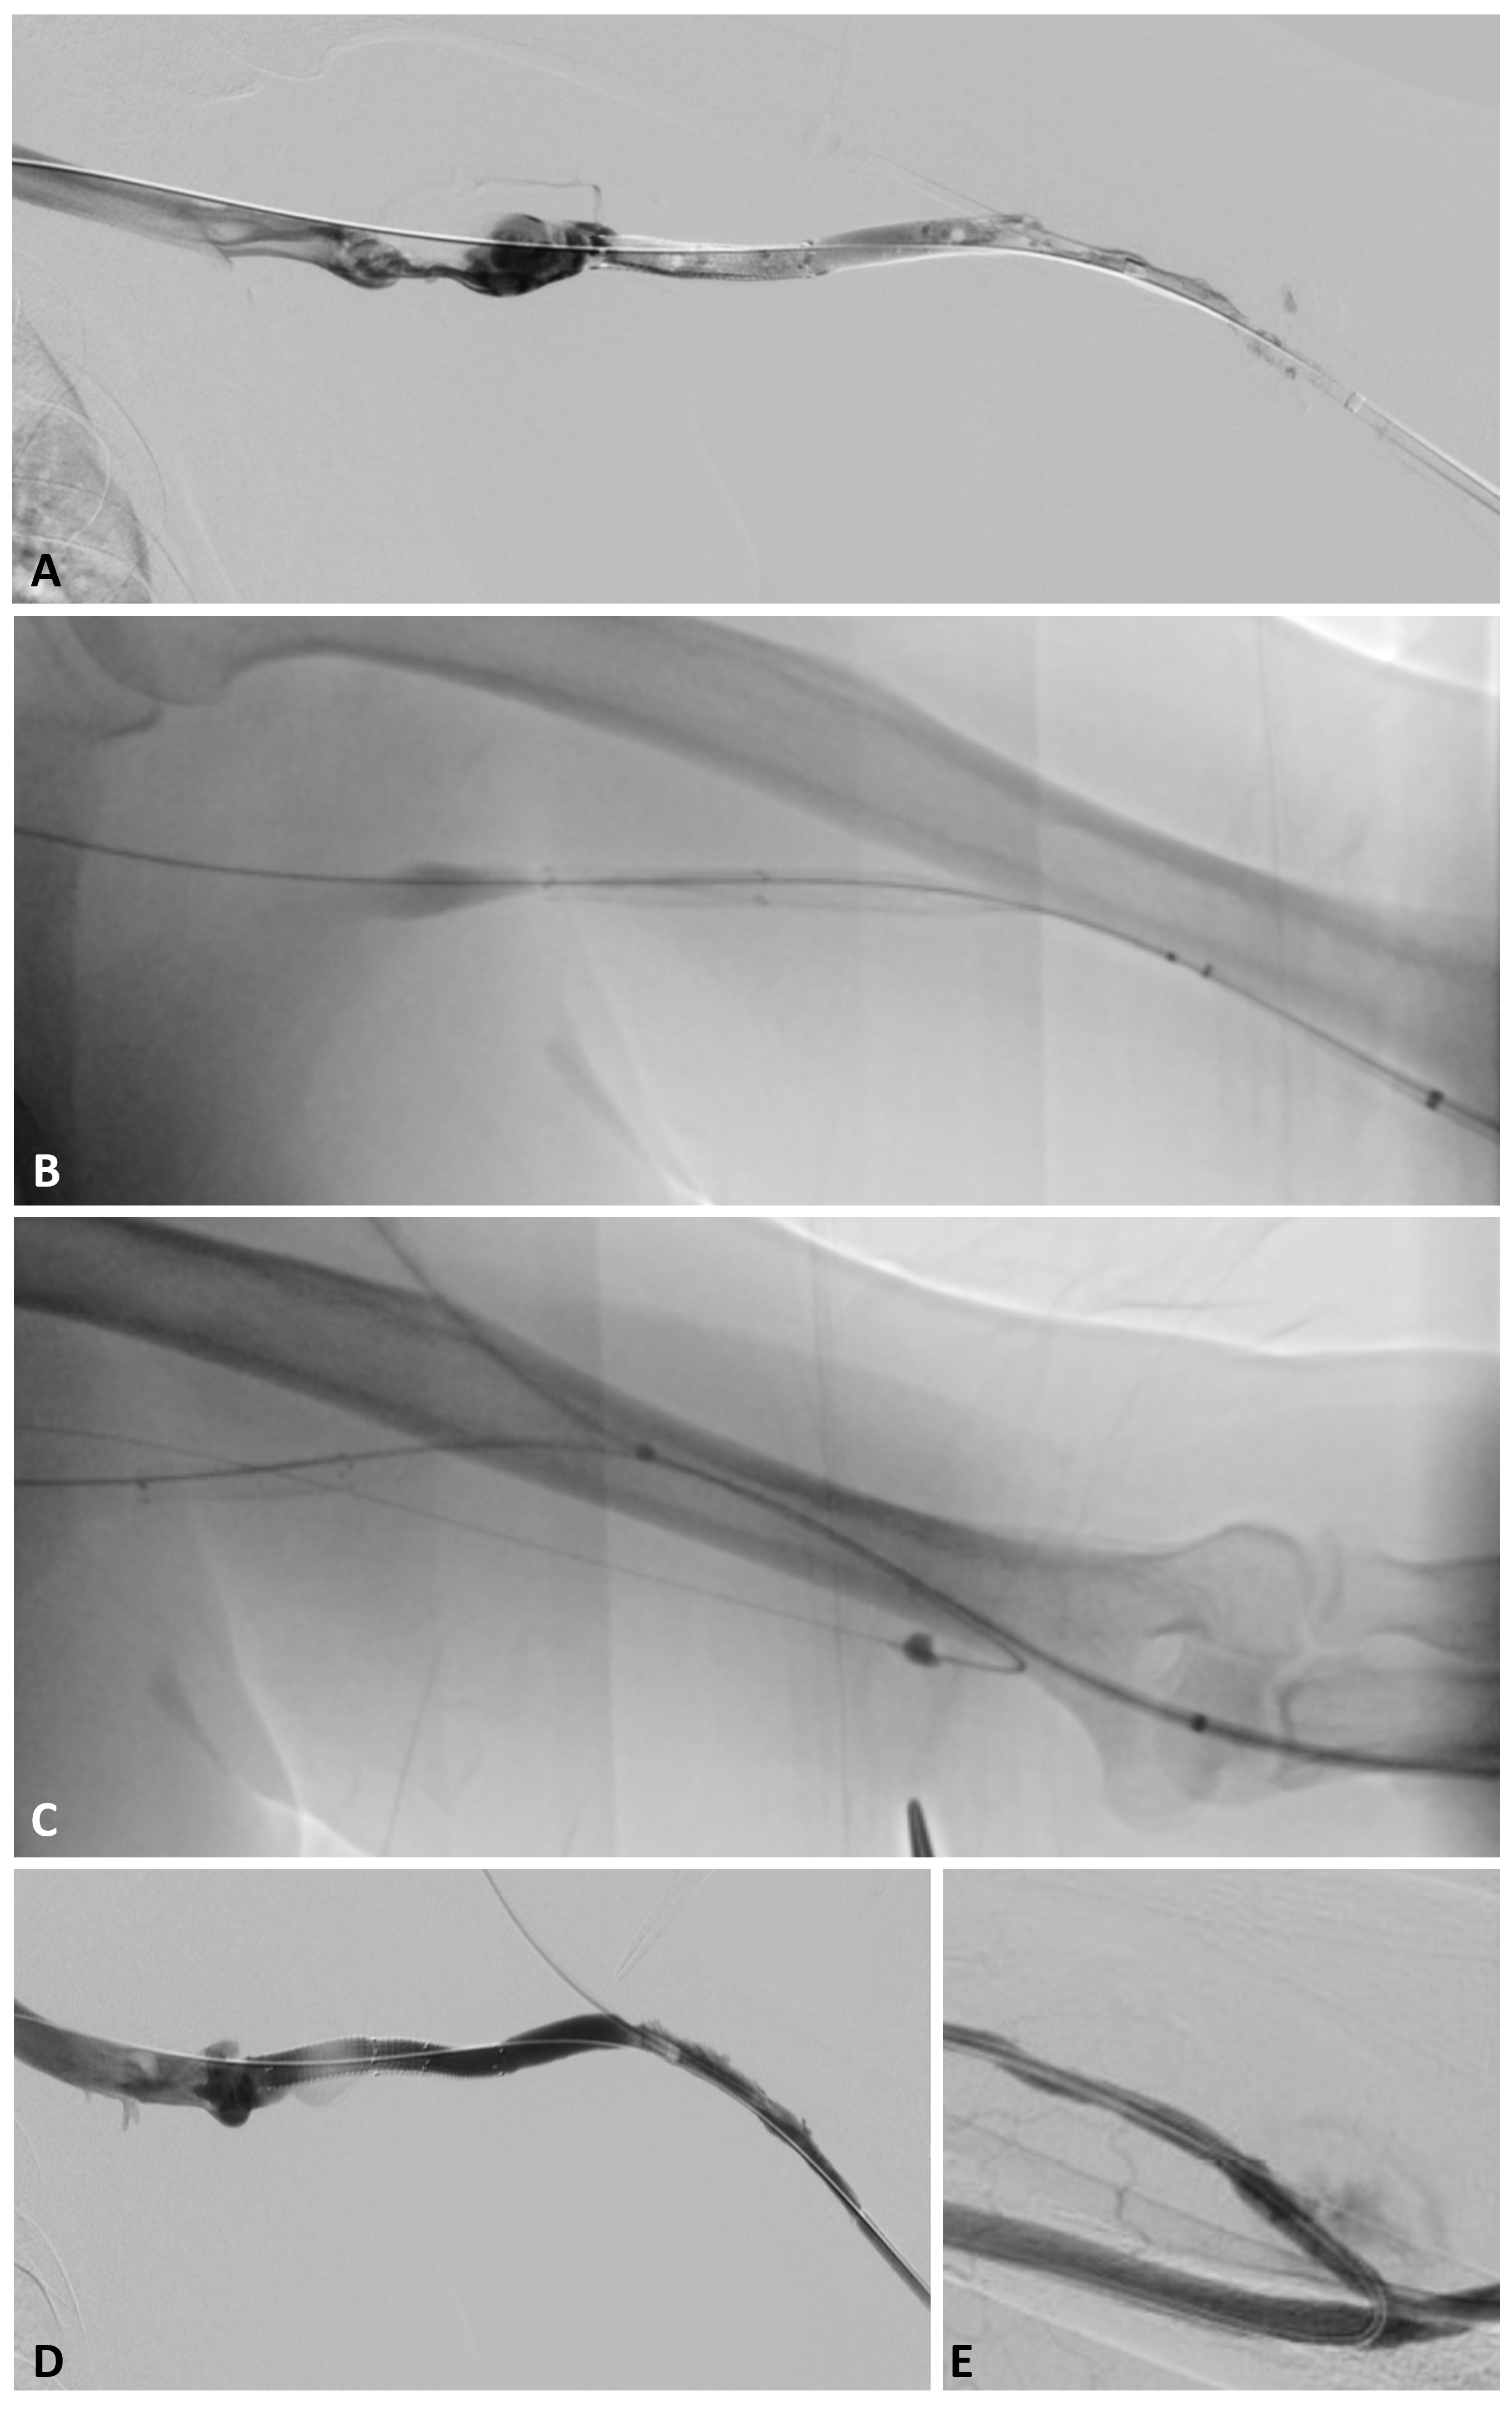

Case 1. A 67-year-old male with history of hypertension, type 2 diabetes, obstructive sleep apnea, dementia, and ESRD on hemodialysis via a left upper extremity arteriovenous graft presented with a clotted access. His left upper arm 7 mm-4 mm tapered Gore-Tex graft (Gore Medical) was surgically placed in October 2021 with anastomoses to the brachial artery and the brachial vein/axillary vein confluence. Thereafter, he underwent repeated conventional declot procedures in December 2021, June 2022, and October 2022. During his second intervention, a 6 mm Viabahn stent graft (Gore Medical) had been deployed across a venous anastomotic stricture. Previous studies had demonstrated chronic filling defects within the access. He was also noted to have increasingly poor sessions in dialysis with decreased flows.

The patient returned in November 2022 with rethrombosis, less than one month after his last declot procedure. Given the history of repeated thrombosis as well as increasing frequency of thrombosis, Interventional Radiology and Nephrology planned for one final attempt at declot. A tunneled dialysis catheter was to be placed if the intervention were to fail.

With sonographic guidance, access was obtained near the arterial anastomosis directed towards the venous outflow. Using Seldinger technique, a short 6 Fr vascular sheath was placed into the access. A Glide hockey catheter was advanced into the central veins over an 0.035-inch angled Glidewire. Pullback venography was performed revealing thrombosis of the outflow vein, previously placed Viabahn stent graft at the venous anastomosis, and dialysis access (Figure 4A). Catheter and wire were then advanced into the inferior vena cava. The wire was exchanged for an .035-inch Advantage Glidewire. After removing the catheter and sheath, the percutaneous access site was dilated to 12 Fr.

The patient was systemically heparinized. The InThrill sheath was placed and deployed, with care taken to stabilize the sheath while exposing its funnel. InThrill thrombectomy catheter was introduced over the wire and deployed with the pin-and-pull technique. A total of 8 separate passes were made in rapid succession, leaving the element on the wire and “flicking” off any extracted thrombus (Figure 4B).

Once the dialysis access, Viabahn stent, and venous outflow were documented to be patent, attention was turned to the arterial end of the dialysis access. During this brief period, the InThrill sheath was flushed periodically with heparinized saline to maintain a column of stagnant saline (as opposed to blood). Using Seldinger technique, retrograde access was obtained using palpation. A Kumpe catheter (Cook Medical) and .035-inch angled Glidewire were used to cross into the brachial artery. Then, the Fogarty maneuver was repeated 3 times over an .018-inch wire (Figure 4C).

After performing the Fogarty maneuver, the graft was immediately noted to be patent, as evidenced by a restored mildly pulsatile thrill throughout the access. As repeat angiography showed a stenosis at the end of the previously placed Viabahn stent graft, an additional 7 mm x 4 cm Viabahn stent graft was placed across the stenosis and into the outflow vein.

To obtain a completion venogram, the dilator was replaced into the InThrill sheath, and the entire system was pulled back over the wire. Venogram performed from the retrograde access showed a patent access with rapid antegrade flow, residual but significantly improved peripheral filling defects within the access vein, and excellent washout of contrast (Figure 4D-E). After closure using an over-the-wire suture technique, the graft was examined. There was minimal pulsatility and an excellent thrill.

The patient has had problem-free dialysis sessions three times a week since the intervention. He has not presented with rethrombosis.